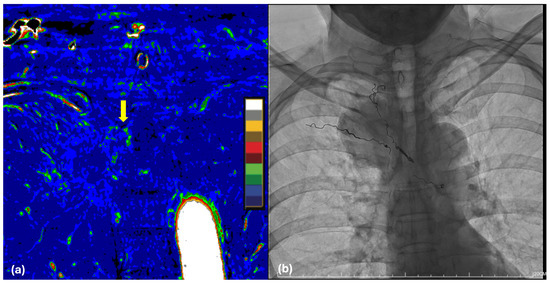

Radiation Dose-Dependent and -Independent Pulmonary Infiltrates in Patients with High-Grade Pneumonitis After Radiochemotherapy and Durvalumab Consolidation for Stage III NSCLC

by Andreas Herz, Aymane Khouya, Maja Guberina, Martin Metzenmacher, Marcel Opitz, Christoph Pöttgen, Gerrit Fischedick, Hubertus Hautzel, Thomas Gauler, Ken Herrmann, Erik Büscher, Servet Bölükbas, Fabian Doerr, Natalie Baldes, Laura Valentina Klüner, Benedikt M. Schaarschmidt, Rüdiger Karpf-Wissel, Jane Winantea, Denise Bos, Verena Jendrossek, Emil Mladenov, Lena Gockeln, Mario Andre Hetzel, Florian Wirsdörfer, Martin Schuler, Martin Stuschke and Nika Guberinaadd Show full author list remove Hide full author list

Diagnostics 2026, 16(6), 827; https://doi.org/10.3390/diagnostics16060827 - 11 Mar 2026

Viewed by 143

Abstract

Background/Objectives: Analysis of the density and spatial distribution of pulmonary infiltrates of patients with high-grade (≥3) pneumonitis after radiochemotherapy and durvalumab consolidation (RT/CTx + IO) was performed in order to define dosimetric hallmarks of the development of infiltrates following this multimodality treatment. [...] Read more.

Background/Objectives: Analysis of the density and spatial distribution of pulmonary infiltrates of patients with high-grade (≥3) pneumonitis after radiochemotherapy and durvalumab consolidation (RT/CTx + IO) was performed in order to define dosimetric hallmarks of the development of infiltrates following this multimodality treatment. Methods: Consecutive patients treated with RT/CTx + IO for stage III NSCLC were retrospectively reviewed with respect to the occurrence of grade ≥ 3 pneumonitis. Lung infiltrates were contoured on follow-up CT scans acquired around the time of maximum pneumonitis expression. The applied dose distribution was overlaid with the follow-up CT using elastic deformation, and infiltrates were binned according to their density in density strata of 50 HU. The dose and density dependence of partial infiltrate volumes per unit lung volume was analyzed using a mixed fixed and random effect model adjusting for patient, density and dose-dependent random effects. Results: Six patients with grade ≥ 3 pneumonitis were identified from 132 patients treated with RT/CT + IO at a comprehensive cancer center. Partial volumes of lung infiltrates captured by follow-up CT with maximum pneumonitis expression ranged from 15.5 to 60.0% (median 39.8%). A significant, systematic dose–response relationship was found for partial lung infiltrate volumes per dose and density bin. A unimodal density distribution of partial lung infiltrate volumes was also found over the infiltrate density range of −1000 to 100 HU. This was determined using a mixed model that adjusted for random effects (p < 0.0001 for both effects, F-test). There was no interaction effect between systematic dose and infiltrate density dependence of the partial infiltrate volumes. The proportion of infiltrate volumes that are attributable to the systematic dose–response relation amounts to a mean of 16.6% of the total infiltrate volume per patient according to this model. Compared to patients with pneumonitis of grade ≤ 2, patients with high-risk pneumonitis had higher partial infiltrate volumes, particularly in the low-dose regions in five grade dose bins up to 20 Gy (AUC = 1.0, p < 0.0001, likelihood-ratio test). Conclusions: Dose-dependent and -independent partial lung infiltrate volumes were found in patients with high-grade pneumonitis after RT/CTx + IO. These results indicate that pneumonitis involves contributions from both radiochemotherapy-induced and immunotherapy-related mechanisms. Full article